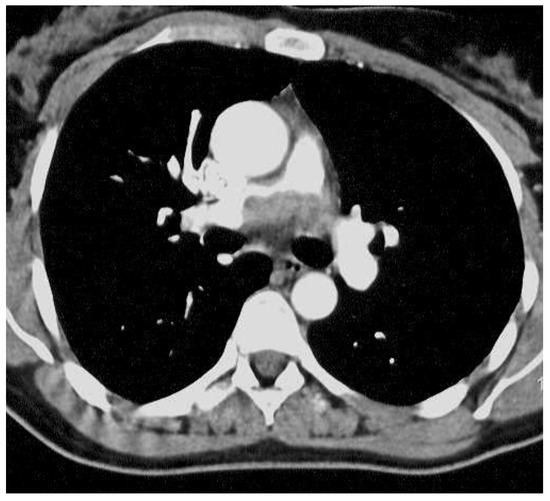

| Location | Pulmonary artery | Right atrium | Pulmonary artery |